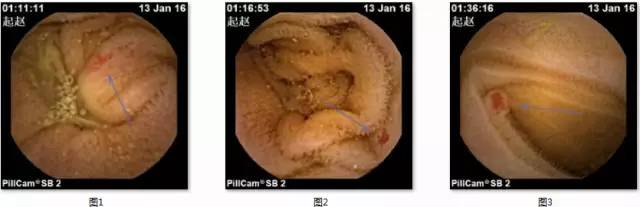

检查后第二天,困扰了赵老伯一家多年的消化道出血原因终于浮出了水面。胶囊内镜非常清楚地显示:在赵老伯的小肠部位散在分布着微小红斑,大小约0.3cm-0.6cm,颜色鲜红,表面黏膜规整,隐约可见血管纹理,部分周围可见白晕,这是典型的毛细血管扩张的形态学特点(图1、图2、图3)。